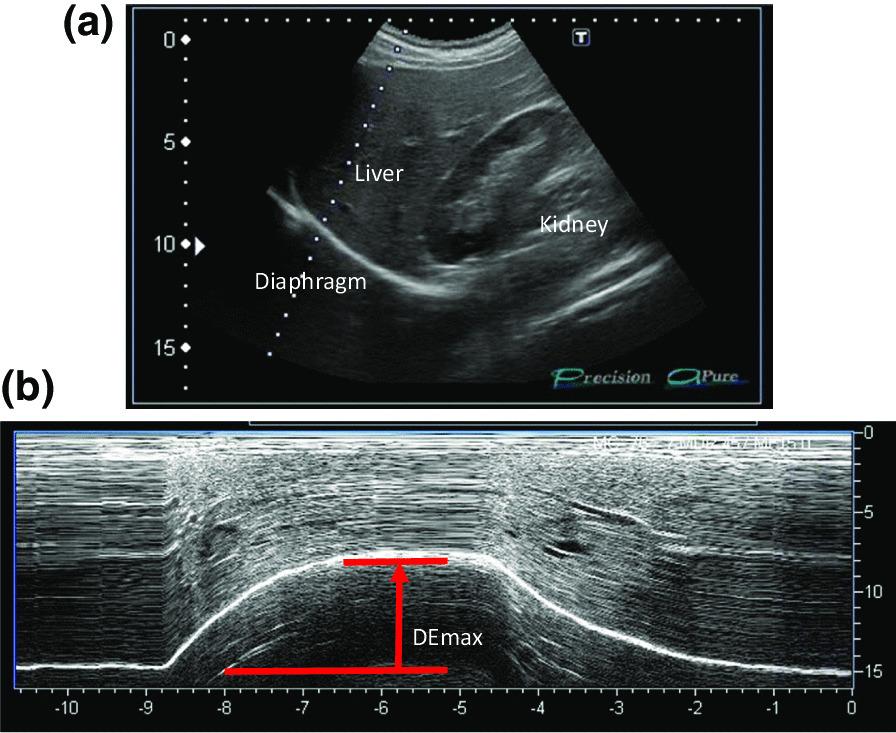

In patients with chronic obstructive pulmonary disease (COPD), the maximum level of diaphragm excursion (DE) is correlated with dynamic lung hyperinflation and exercise tolerance. This study aimed to elucidate the utility of DE to predict the improvement in exercise tolerance after pulmonary rehabilitation (PR) in patients with COPD.

METHODS

This was a prospective cohort study. Of the 62 patients with stable COPD who participated in the outpatient PR programme from April 2018 to February 2021, 50 completed the programme. Six-minute walk distance (6MWD) was performed to evaluate exercise tolerance, and ultrasonography was performed to measure DE. Responders to PR in exercise capacity were defined as patients who demonstrated an increase of > 30 m in 6MWD. The receiver operating characteristic (ROC) curve was used to determine the cut-off point of DE to predict responses to PR.

RESULTS

Baseline levels of forced expiratory volume in 1 s, 6MWD, maximum inspiratory pressure, DE and quadriceps muscle strength were significantly higher, and peak dyspnoea of modified Borg (mBorg) scale score was lower in responders (n = 30) than in non-responders (n = 20) to PR (p < 0.01). In multivariate analysis, DE was significantly correlated with an increase of > 30 m in 6MWD. The area under the ROC curve of DE to predict responders was 0.915, with a sensitivity and specificity of 83% and 95%, respectively, at a cut-off value of 44.9 mm of DE.